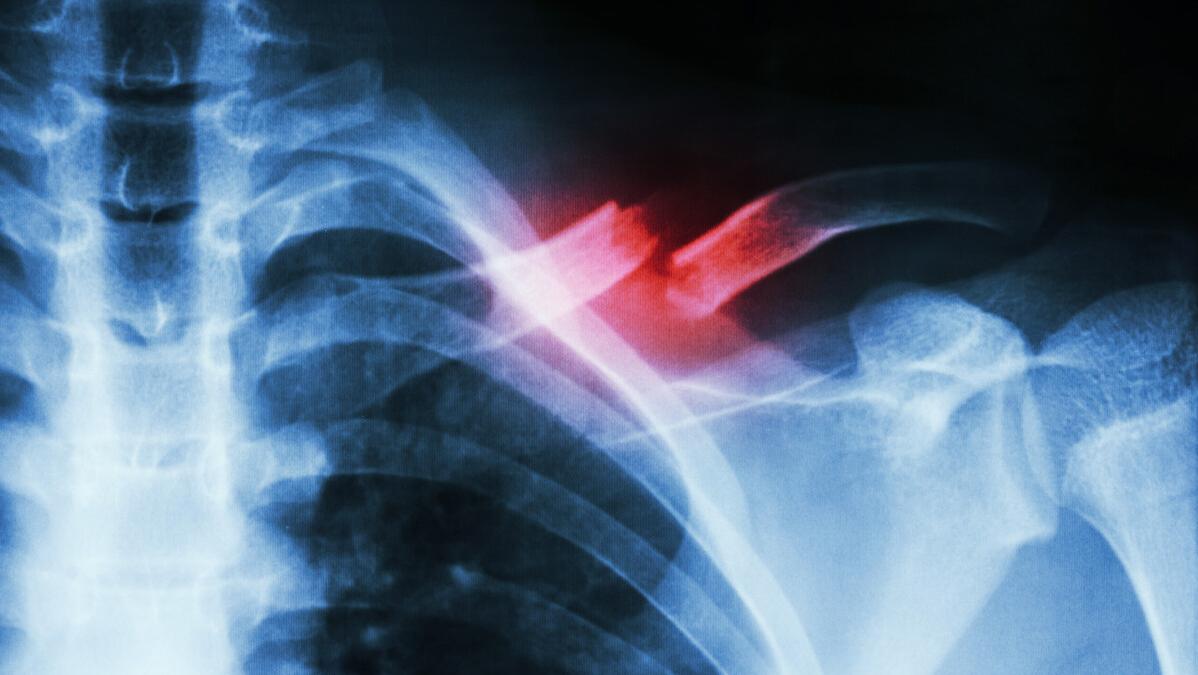

锁骨骨折是人体最容易发生的骨折之一,其机制往往是直接撞击或摔倒时手部前伸产生的传导应力。锁骨骨折好发于锁骨中段,约占80%,其次为锁骨远端、锁骨近端。

锁骨骨折分型

Allman将锁骨骨折分为三组:1组为锁骨中段骨折(80%)、2组为锁骨远端骨折(15%)、3组为锁骨近端骨折(5%)。Craig(克雷格)进一步详细分型,其中将第2组(锁骨远端骨折)分为5个亚型。着重了解一下第2组的5个亚型。